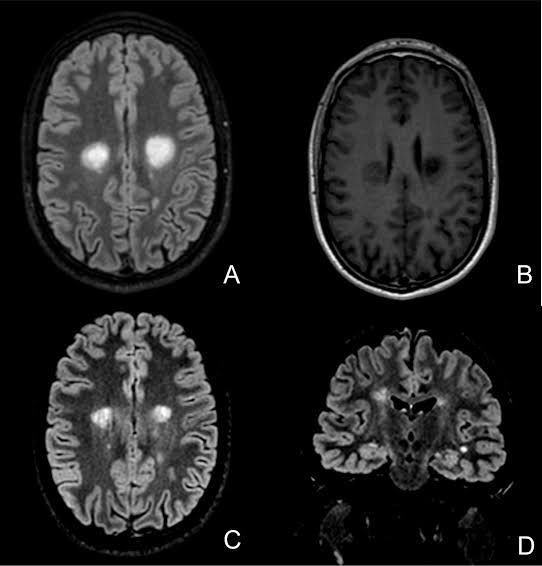

Symptoms of schilder's sclerosis

Schilder's disease often happens right after an infectious illness. It might start with an overall feeling of discomfort and fever.